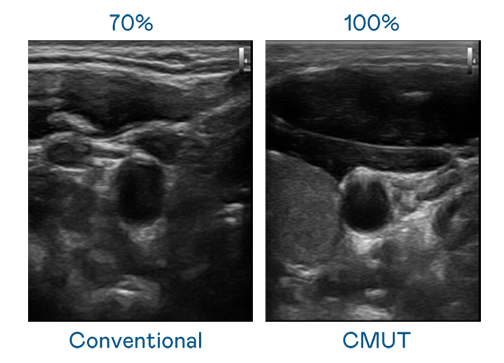

CMUT 技術是一種用電容式微機電元件來產生超音波訊號的技術。與傳統 PZT 壓電式技術相比,CMUT 頻寬增加 30%,更寬頻的超音波訊號讓影像解析度大幅提升,是實現高影像品質醫療超音波掃描、促進精準醫療發展的關鍵技術。

超音波影像的解析度高低,首先取決於探頭能發出的訊號頻寬。人生就是博 CMUT 可提供高清晰的超音波訊號,提供高頻寬、高靈敏度、影像紋理細節更高的超音波影像,協助醫護人員縮短影像判讀時間及利用精準的醫療影像進行診斷。